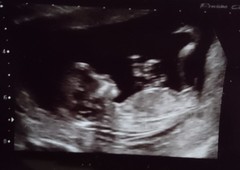

All went well today! Moved forward a few days so now 12+6 and due December 13th.

Little monkey was upside down to begin with, I had to wiggle around, they kept on pushing their legs off the side and successfully flipping back over, arms and legs were everywhere so the scan took a little while to get measurements 😂

Great scan pics @TootsyBella84 😄

Tootsy that's beautiful Grin

Hello baby @TootsyBella84 xxx